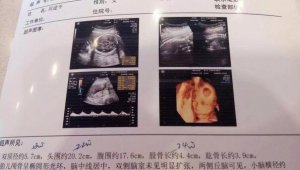

四维彩超怎么看男女?看这7个数据

[生男生女]从怀孕那一刻起准爸妈恨不得把每一天每一秒乃至一点一滴都记录下来,最为激动人心的便是数着四维检查的日子早早到来,因为这样可以近距离的看到自己的小宝宝,甚至通过影像都能听到